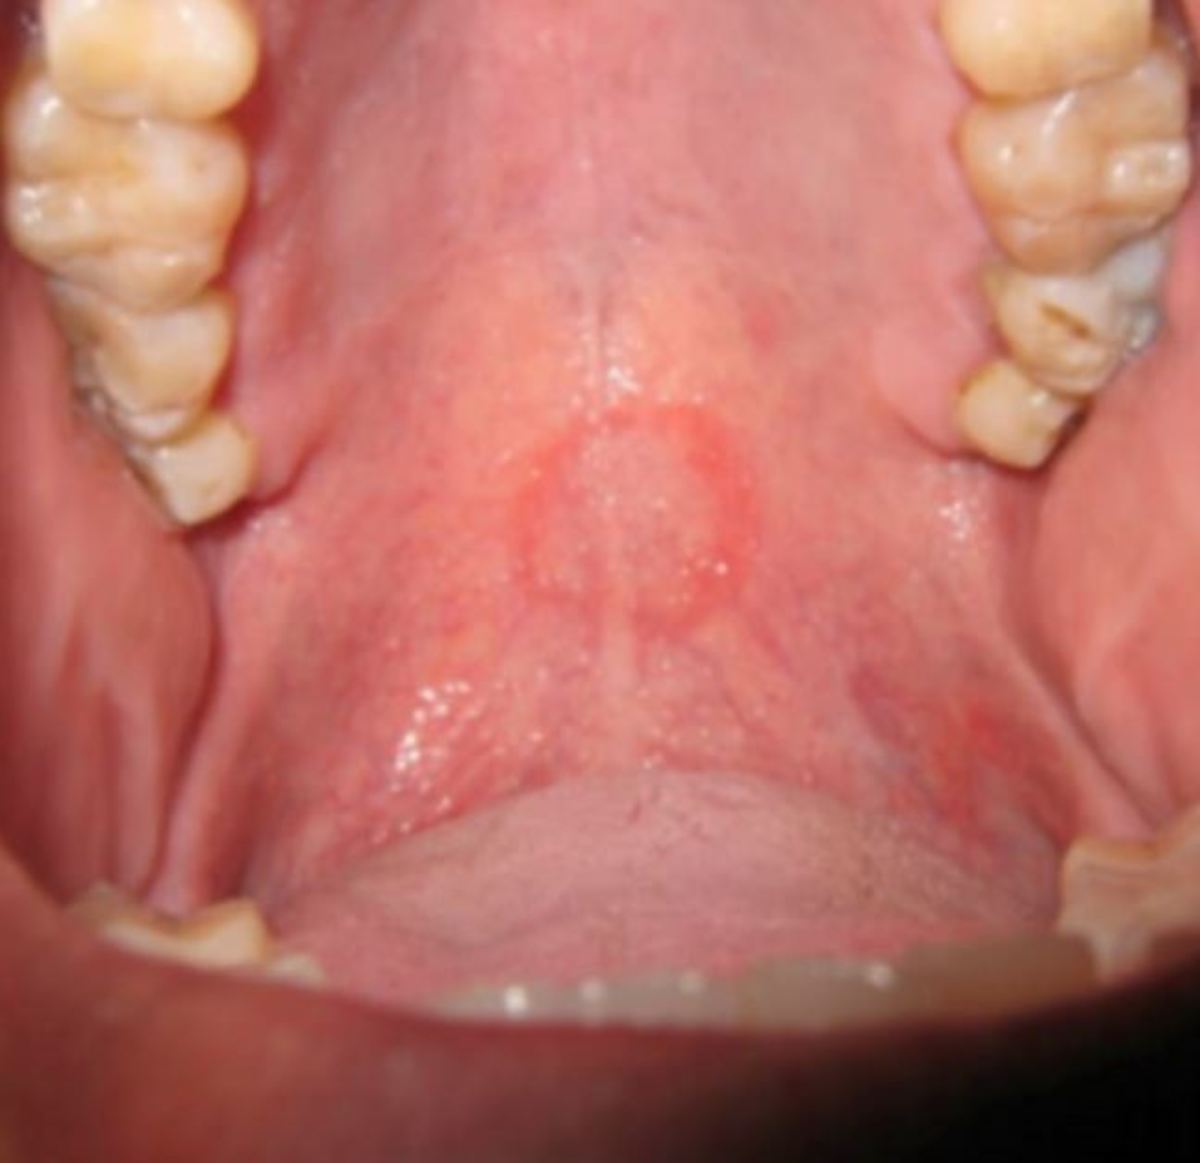

Βλέπετε το σημάδι στον ουρανίσκο του; Το έπαθε από το στοματικό σεξ!

Οι οδοντίατροι που τον εξέτασαν απόρησαν με το κόκκινο σημάδι στον ουρανίσκο του 47χρονου και μετά από κάποιες ερωτήσεις που του έκαναν, έφτασαν στο συμπέρασμα ότι το σημάδι προκλήθηκε από στοματικό σεξ που είχε κάνει ο 47χρονος σε άλλο άτομο!

Το περίεργο σημάδι στον ουρανίσκο του 47χρονου προκλήθηκε από το στοματικό σεξ, σύμφωνα με τους γιατρούς

Εκείνος συμβουλεύτηκε και άλλους συναδέλφους του και τελικά συμφώνησαν ότι το περίεργο σημάδι -το οποίο είναι γνωστό στον ιατρικό κόσμο ως ερύθημα (erythmea)- είχε προκληθεί από στοματικό σεξ.

Η ομάδα, με επικεφαλής τον δρ. Luis Alberto Mendez, εξήγησε: «Η επαφή του ουρανίσκου με το πέος μπορεί να προκαλέσει αιμάτωμα λόγω τραύματος».

Πρόσθεσαν, επίσης, ότι η διαστολή των αιμοφόρων αγγείων στο στόμα που συμβαίνει κατά το στοματικό σεξ μπορεί επίσης να έχει συμβάλλει στην μορφή του σημαδιού στον ουρανίσκο του 47χρονου. Ο τελευταίος, παραδέχτηκε στους γιατρούς ότι ήταν σεξουαλικά ενεργός με άλλους άνδρες, καθώς επίσης ότι είχε κάνει προσφάτως χρήση μαριχουάνας και κοκαΐνης. Πρόσθεσε επίσης ότι προσφέρει τακτικά στοματικό σεξ σε άνδρες και ότι η πιο πρόσφατη φορά που συνέβη ήταν τρεις ημέρες πριν πάει στον οδοντίατρο.